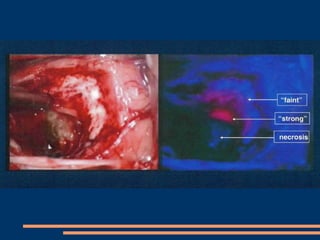

La 5-ALA (suite) En éclairant « en bleu » (longueur d’onde différente), la tumeur apparaît “en rose” , il suffit de changer le mode d’éclairage du microscope. Donc limites de  résection plus précises, moins de résidus tumoraux. Visualisation en direct des cellules cancéreuses qui ont intégré la 5-ALA.

Utilisation 5-ALA : lumière blanche et lumière bleue

Concrètement : Molécule administrée  per os  dans les 4 à 6h avant l‘anesthésie, à la dose de 20 mg/kg Pendant l'opération : changement de lumière du microscope fait apparaître les cellules qui ont intégré la 5-ALA : visualisation plus précise de la tumeur, ses limites.